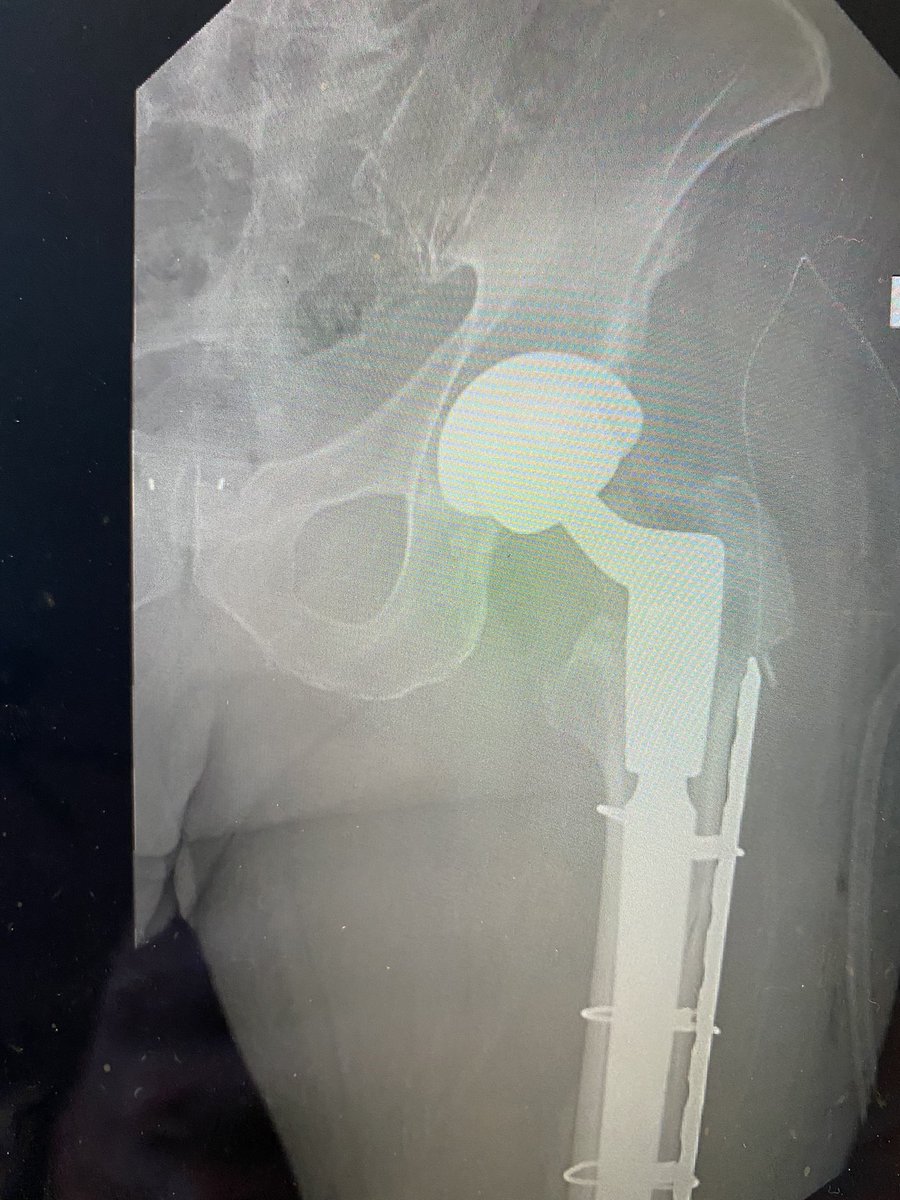

@depurhro revised plus ORIF in my hands. In older patients I have also tended to extend fixation across the entire femur for prophylactic femur protection. Pics of recent case but press fit stem. Slightly different concepts. ?anyone else prophylactic long femur fixation?